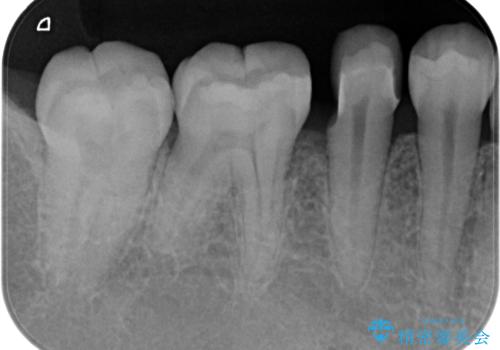

歯と歯の間の虫歯 セラミックインレーでの修復処置

- 検査の結果、歯と歯の間に虫歯が確認された患者様です。

虫歯を除去した後、セラミックインレーで修復処置を行います。

- 右下5 セラミックインレー 77,000円費用は治療当時の料金となります

レントゲン画像では写りにくい小さな虫歯も発見したため、そこも含めた形での修復処置を行いました。